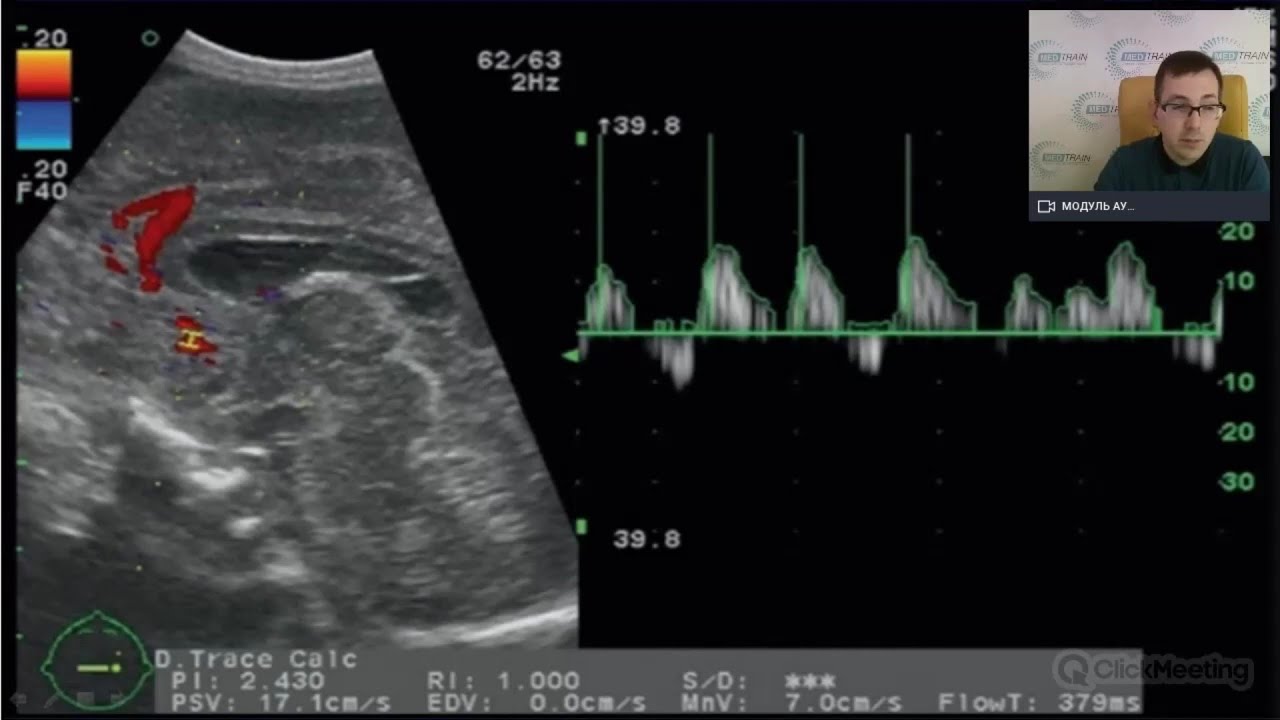

Оптимизация изображения. Возможности визуализации мозжечка. Оценка кровоизлияний в мозжечок

Полезное видео, которое посвящено нейросонографии, а именно оптимизации изображения, возможностям визуализации мозжечка и оценке кровоизлияний в мозжечок.